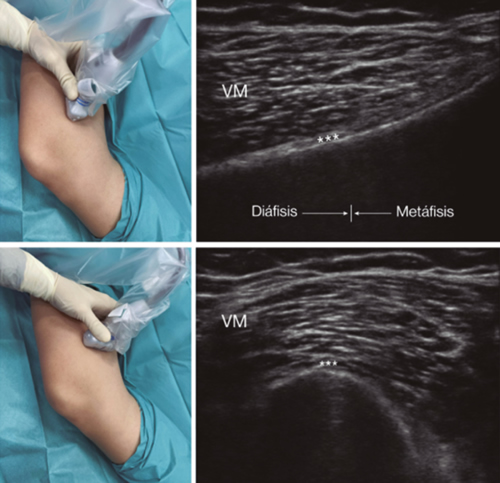

Fig. 3. Sonoanatomy and technique for performing superior medial genicular nerve block (SMGN). The transducer is located on the distal long axis of the femur and once the position of the SMGN (asterisks) is known, the probe is rotated 90 degrees to obtain a view of the femur short-axis (don't forget to keep the same depth that we find the SMGN on the long axis). VM (vastus medialis).

In order to achieve a correct location of anatomical landmarks by ultrasound we must place the patient in supine position with the knee flexed and a pillow under the popliteal fossa (14,16,19).

After performing knee asepsis/antisepsis, surgical field placement, and the sterile sheath of the high frequency linear transducer, we proceed to locate the SMGN (Figure 3). Placing the probe in a coronal plane on the inner face of the knee, we slide it cranially to visualize the junction of the metaphysis to the femoral diaphysis and the superior medial genicular artery/nerve (ASMGN), usually located near the periostium of the femur (if this neurovascular structure is not found, the junction between metaphysis and femoral diaphysis is taken as a reference). The mid-point of the transducer corresponding to ASMGN is then marked on the skin and the transducer is rotated to be placed in the transverse or axial plane to view ASMGN on the short axis (if this structure is not visible, confirm that we are at 50 % depth of the femur). In this cross-section the needle of the TRF is advanced in plane from anterior to posterior toward the ASMGN or to a depth of 50 % of the thickness of the femur. Finally, the transducer is rotated 90° again, leaving it in a coronal plane to check that the needle tip is near the ASMGN or the junction of the metaphysis and femoral diaphysis (14,16,19).

To locate the IMGN (Figure 4), we placed the transducer in a coronal plane on the inner face of the knee, sliding it caudally to identify the diaphysis junction with the tibial metaphysis and the inferomedial genicular artery/nerve (AIMGN). And we repeat the same steps we used for SMGN. If the AIMGN is not found, the reference to be taken shall be the depth of 50 % of the thickness of the tibia (14,16,19).